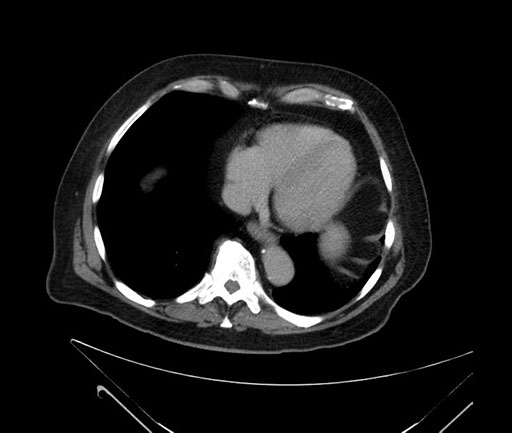

Imaging Analysis

Look through the patient's CT scan to identify any areas of concern for the necessary procedure.

Based on your CT findings, which issue(s) would give reason for "planned slowing down moment(s)" in this case?

Considering a standard Whipple procedure, what step(s) of the operation would you do differently in this case?